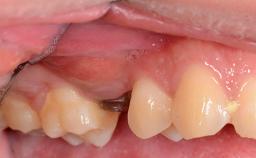

Her chief complaint was her inability to masticate efficiently due to the recent loss of her mandibular second premolars and first molars bilaterally. She expressed a desire for fixed prostheses in the shortest possible time due to her advanced age, requesting that replacement teeth should look as natural as possible. She was otherwise comfortable and not experiencing any symptoms from her teeth.

Jaw Mandible

Area Posterior

# of Teeth 4

# of Implants 4